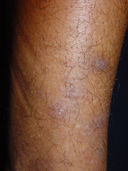

Amiloidose